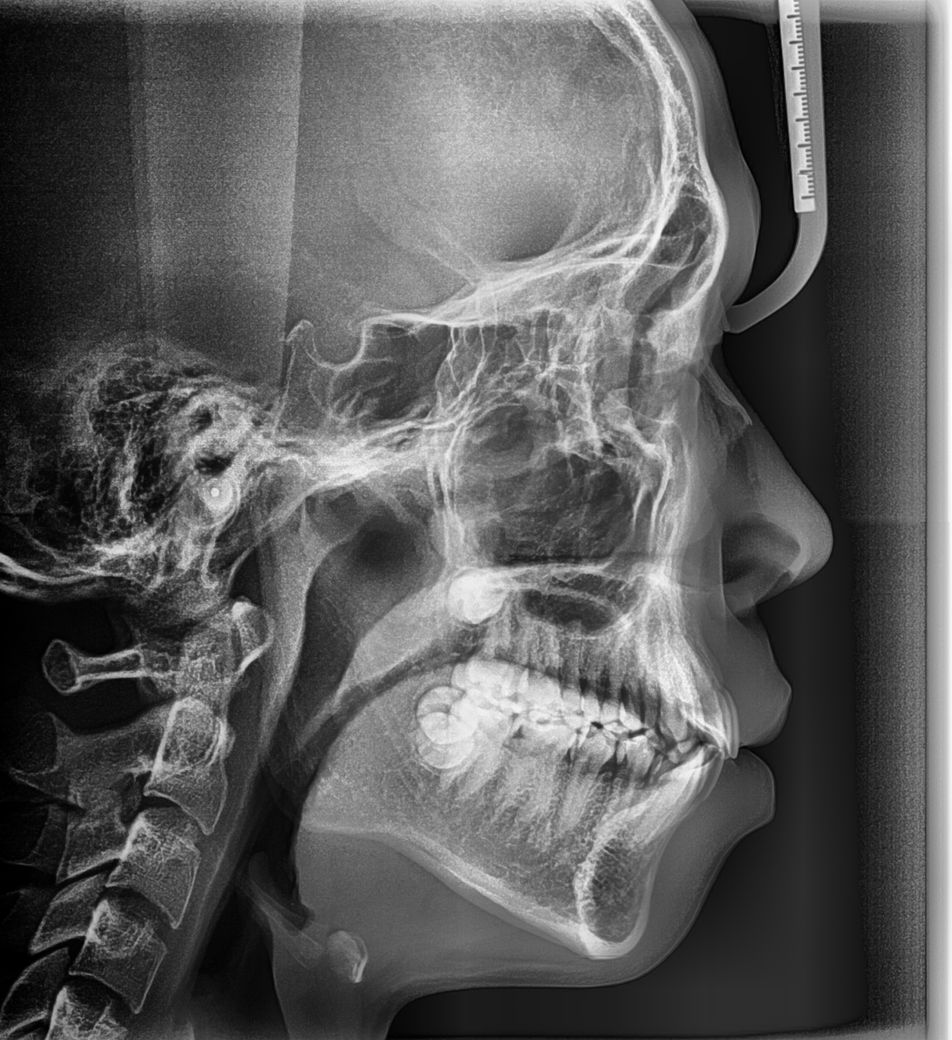

기존교정을 끝냈고 사랑니 발치후 스크류추가교정을 하게되면 치아가 1~2mm정도 뒤로 들어간다는데 입을 들어가게 하고싶어서 하고 싶습니다

아래는 현재상태에요 여기서 1~2mm치아가 들어가면 입이 얼마나 들어갈지요..

위에4개 는 교정 전 사진

그다음 2개는 교정중 1년 8개월 됬을때

다음은 교정후 현재상태에요